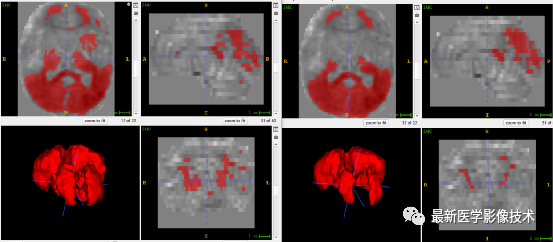

5、验证集分割结果

左图是金标准结果,右图是预测结果。